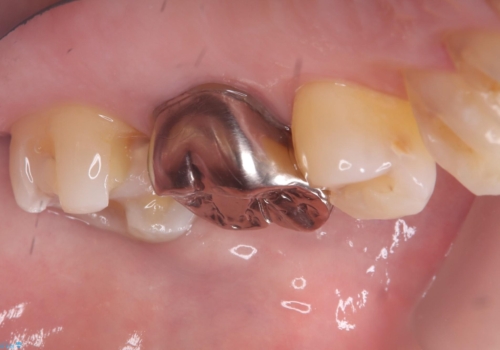

- 主訴:フロスを通したら、詰め物が取れた。適合の良いものを入れたい。

保険適用のメタルインレーが脱離しており、適合重視・咬合力が強いことからゴールドインレーでのやり替えとなりました。

フロスを通しインレーが脱離したことから、インレーと歯質との境に段差(適合不良)があった可能性があり、適合の良さや咬合力による補綴物の破折リスクを考慮し、ゴールドインレーでのやり替えとなりました。